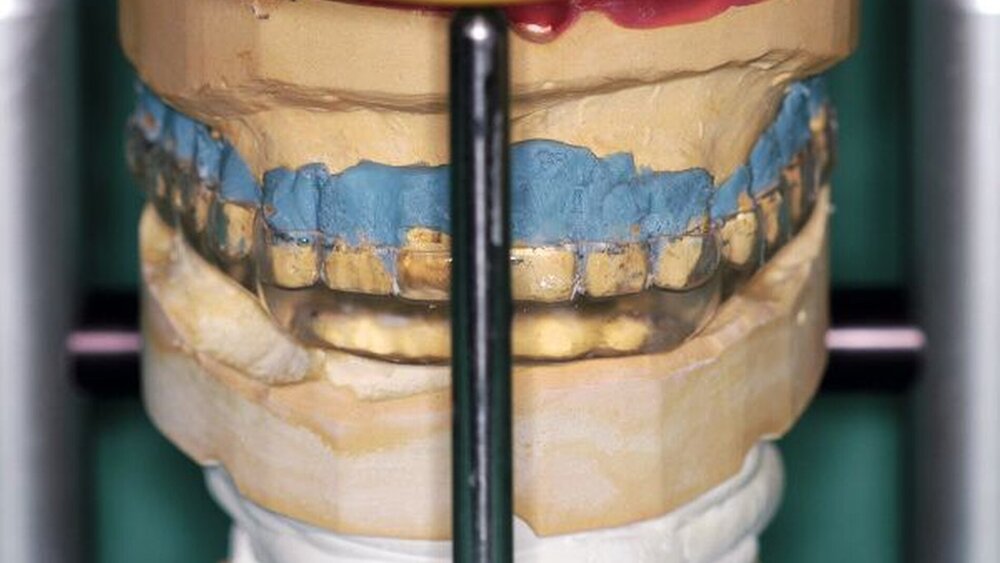

Die Abformungen des OK und des UK erfolgten als Korrekturabformung unter Verwendung eines A-Silikons. Zur Darstellung der subgingival liegenden Präparationsgrenzen wurden mit Adstringentien getränkte, geflochtene Retraktionsfäden in die Sulci aller Zähne eingelegt. Eine adäquate Trocknung der abzuformenden Bereiche wurde durch die Verwendung von Kompressions-Wattekappen, die auf den einzelnen Zähnen platziert wurden, durch Parotispflaster sowie durch eine konstante Absaugung erreicht. Um ein möglichst langes Verarbeitungsintervall zu erzielen, wurde das verwendete Silikon zuvor im Kühlschrank gelagert [Wöstmann et al., 1992; Wöstmann et al., 1999]. Nach erfolgter Abformung wurde ein Gesichtsbogen zur individuellen Übertragung des Oberkiefermodells in den Artikulator angelegt, danach wurden die Provisorien des I- und IV-Quadranten wieder befestigt. Nun wurden partielle interokklusale Registratschlüssel mithilfe eines intraoral anwendbaren Autopolymerisats im Bereich des II- und III-Quadranten angefertigt und beschliffen. In einem zweiten Schritt wurden die Provisorien im I- und IV-Quadranten entfernt und die partiellen interokklusalen Registratschlüssel des II- und III-Quadranten eingesetzt. In dieser Position wurden nun ebenfalls Registratschlüssel im I- und IV-Quadranten angefertigt und beschliffen. Durch dieses Vorgehen war es möglich, die im Rahmen der Registration ermittelte Position – unter Einbeziehung der präparierten Zahnhartsubstanz – auf die Modellsituation des Arbeitsmodells zu übertragen. Abschließend erfolgte die Farbauswahl. Die Arbeitsmodelle wurden mithilfe des zuvor angelegten Gesichtsbogens und der erstellten Registratschlüssel in einen teiljustierbaren Artikulator übertragen. Im Labor erfolgte die Herstellung der Nichtedelmetall-Gerüste der Einzelkronen 22, 32, 31, 41 und 42, die der Brücken 12 bis 21, 35 bis 37 und 43 bis 46 sowie die der Nichtedelmetall- Primärkronen 13, 14, 23 und 24.

Nach durchgeführter Verblendung und Anfertigung des Sekundärgerüsts der partiellen oberen Prothese sowie Anfertigung einer separaten Wachsaufstellung wurden die Kronen und Brücken erneut anprobiert, um etwaige Änderungen die Farbe der Restaurationen betreffend vor dem Glasurbrand durchführen zu können. Zudem wurde die Sekundärkonstruktion der partiellen oberen Prothese auf ihre Passgenauigkeit hin überprüft. In einem letzten Schritt erfolgte dann die Beurteilung der Okklusion der Wachsaufstellung in Relation zu den angefertigten Kronen und Brücken.

Als Methode für die Montage der Modelle zur Modellanalyse wurde das Checkbiss-Registrat mittels einer Beauty-Pink-Platte und Aluwachs angewendet. Die Montage der Modelle zur Herstellung der okklusal adjustierten Stabilisierungsschiene erfolgte mittels des intraoralen Pfeilwinkelregistrats. Statistisch zeigen sich zwischen den einzelnen Registrationsverfahren keine signifikanten Unterschiede [Utz et al., 2002]. Da es sich jedoch im vorliegenden Fall um einen Patienten mit reduzierter Dentition handelt, bietet das intraorale Pfeilwinkelregistrat unter Verwendung laborgefertigter Registrierbehelfe eine praktikable, reproduzierbare und sichere Methode.